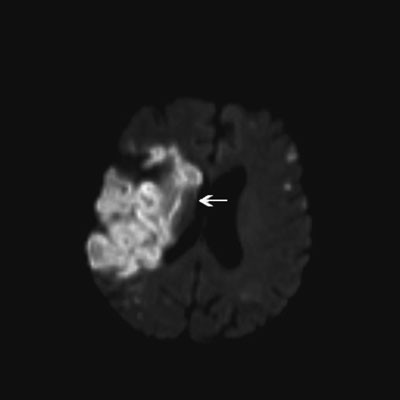

CT av hjernen ble tatt noen timer etter innleggelsen, og viste sannsynlig ferskt infarkt omkring høyre fissura Sylvii og spredte lavattenuerende forandringer i begge hemisfærer. Spinalpunksjon viste normalt celletall. MR av hjernen etter spinalpunksjon bekreftet iskemiske lesjoner (diffusjonsavvik) i begge cerebrale og cerebellære hemisfærer (fig 1a, fig 1b).

Operativ behandling av primærtumor i lungen ble vurdert, men til tross for kombinasjonsbehandling med dalteparin og acetylsalisylsyre fikk pasienten i påvente av operasjon akutt venstre hemiparalyse, forverring av kognitiv svikt og ble helt pleietrengende. Hun hadde D-dimer > 20 mg/l (normalt 0,00 – 0,50) og troponin-T 3722 ng/l (normalt < 15). MR av hjernen viste et stort infarkt i høyre a. cerebri medias forsyningsområde (fig 2). Pasienten ble tverrfaglig vurdert som inoperabel på grunn av et aggressivt forløp med raskt tilbakevendende og multiple organtromboser. Risikoen for nye tromboemboliske hendelser som følge av perioperativ seponering av antikoagulasjonsbehandling ble vurdert som høyere enn den mulige operative nytten. Hun ble utskrevet til sykehjem og fikk palliativ strålebehandling mot mediastinum og høyre fossa supraclavicularis på grunn av infiltrative lymfeknuter subcarinalt, pretrakealt og i øvre høyre mediastinum. Som komplikasjon til hjerneinfarktene utviklet hun epilepsi. Klopidogrel ble kombinert med dalteparin og acetylsalisylsyre på grunn av akutt hjerteinfarkt med ST-segmentelevasjon under denne innleggelsen. Til tross for aggressiv antikoagulasjonsbehandling rapporterte datteren senere om en forbigående episode hvor det paretiske venstre beinet ble smertefullt, hvitt og kaldt, suspekt på perifer arteriell emboli. Ett år etter sykdomsdebut døde pasienten av hjerte- og lungesvikt betinget av betydelig tumorvekst. Autopsi ble ikke utført.